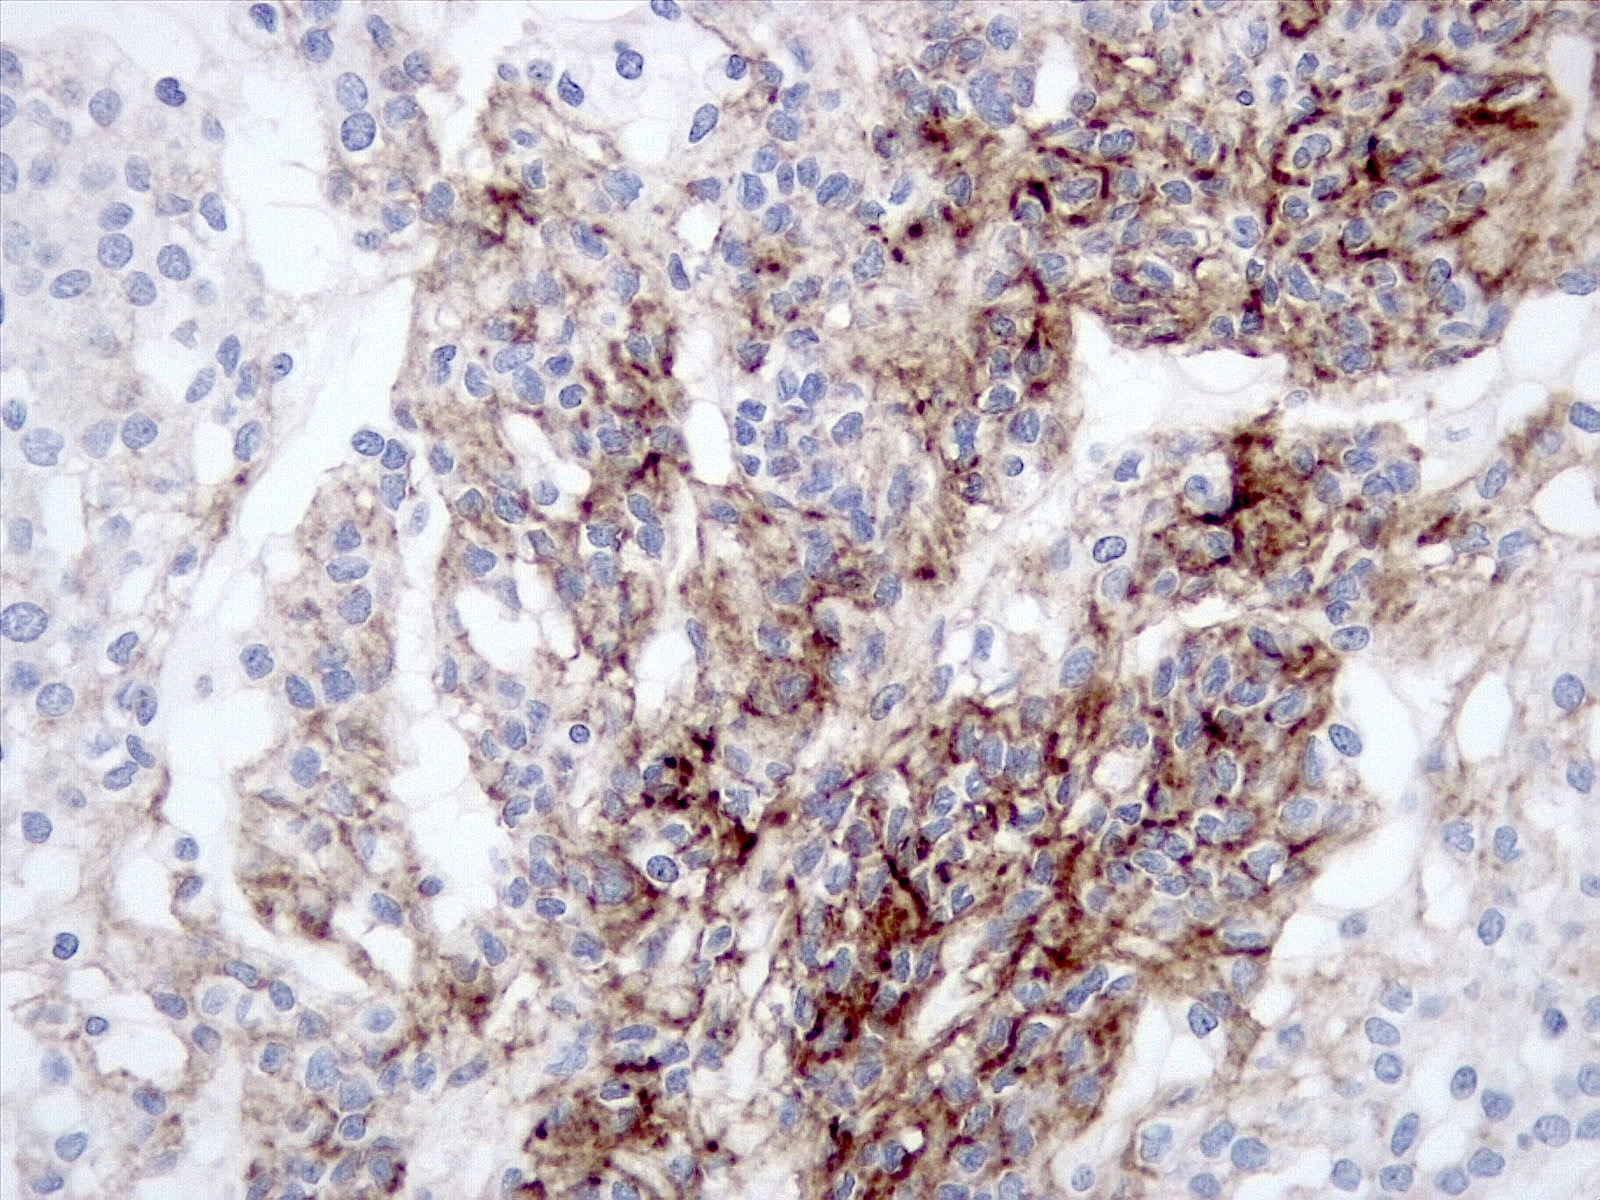

Microscopic (histologic) description

- Histologically reminiscent of chordoma, consisting of epithelioid cells or spindle cells (often partly vacuolated) that are arranged in cords within a pale basophilic myxoid matrix (Am J Surg Pathol 2000;24:899, J Neurooncol 2010;100:465, Histopathology 2013;62:1002)

- Chordoid morphology must be the predominant pattern for diagnosis of chordoid meningioma and CNS WHO grade 2 designation

- Interspersed areas of more typical meningioma are frequent but pure chordoid cases may be seen (Am J Surg Pathol 2000;24:899, J Neurooncol 2010;100:465, Histopathology 2013;62:1002)

- Atypical features may be seen, including mitoses, brain invasion, spontaneous necrosis, macronucleoli, increased cellularity, sheeting or small cells with a high N:C ratio (Am J Surg Pathol 2000;24:899, Acta Neuropathol Commun 2022;10:56, Histopathology 2013;62:1002)

- Lymphoplasmacytic infiltrate in 59.5% (Am J Surg Pathol 2000;24:899)

Microscopic (histologic) images

Positive stains

- EMA (92.6%) (World Neurosurg 2016;93:198)

- Progesterone receptor (92.3%) (World Neurosurg 2016;93:198)

- SSTR2A (Neurosurg Rev 2022;45:467)

- Podoplanin (80%) (Am J Surg Pathol 2009;33:669)

- Mucoid matrix is red on mucicarmine stain, pink in the PASD reaction and bright blue on Alcian blue stain at pH 2 (Am J Surg Pathol 2000;24:899)